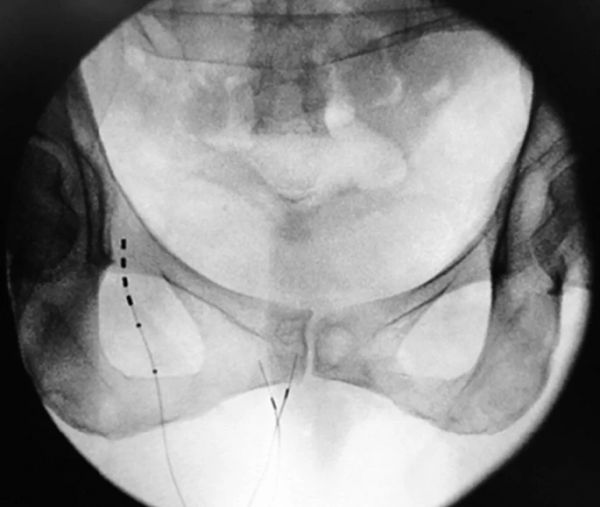

4.通过坐骨直肠间隙经皮进入阴部神经,将孔针从内侧到外侧方向穿过坐骨结节,朝向坐骨棘(图10.7)。当针头通过时,以 5 Hz 和 5 伏进行刺激以识别神经。神经可以通过在 EMG 上看到复合肌肉动作电位 (CMAP) 和检查时的肛门眨眼来识别。

6.在透视下验证针的位置(图10.8)。然后以类似于骶神经调节程序的方式放置定向导丝和引导引入器。

8.导线位置应通过荧光检查在前后(图10.9)和侧向(图10.10)位置进行确认。

图 10.7

阴部针插入。

图 10.8

透视上的针位置。

图 10.9

前后引导位置。